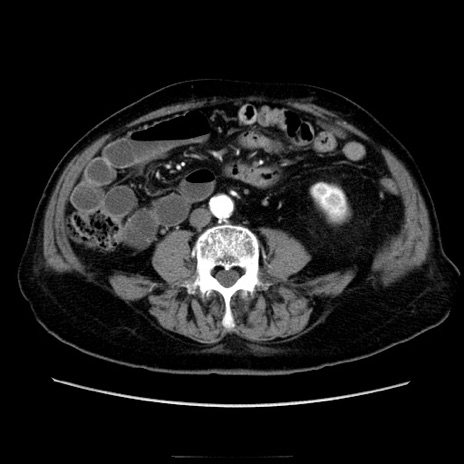

症例21(横断像)

【症例】70歳代男性

【主訴】腹痛

【現病歴】肝硬変・肝細胞癌にてかかりつけの方。約9時間前に食後より腹痛出現。症状が徐々に増悪し、嘔吐出現したため来院。

【既往歴】肝硬変、肝細胞癌(RFA、TACE後)

【身体所見】意識清明、表情苦悶様、BT 36℃、BP 129/78mmHg、P 88bpm、SpO2 97%(RA)、右上腹部から心窩部にかけて圧痛あり、反跳痛なし、筋性防御あり。

【データ】WBC 5800、CRP 0.16